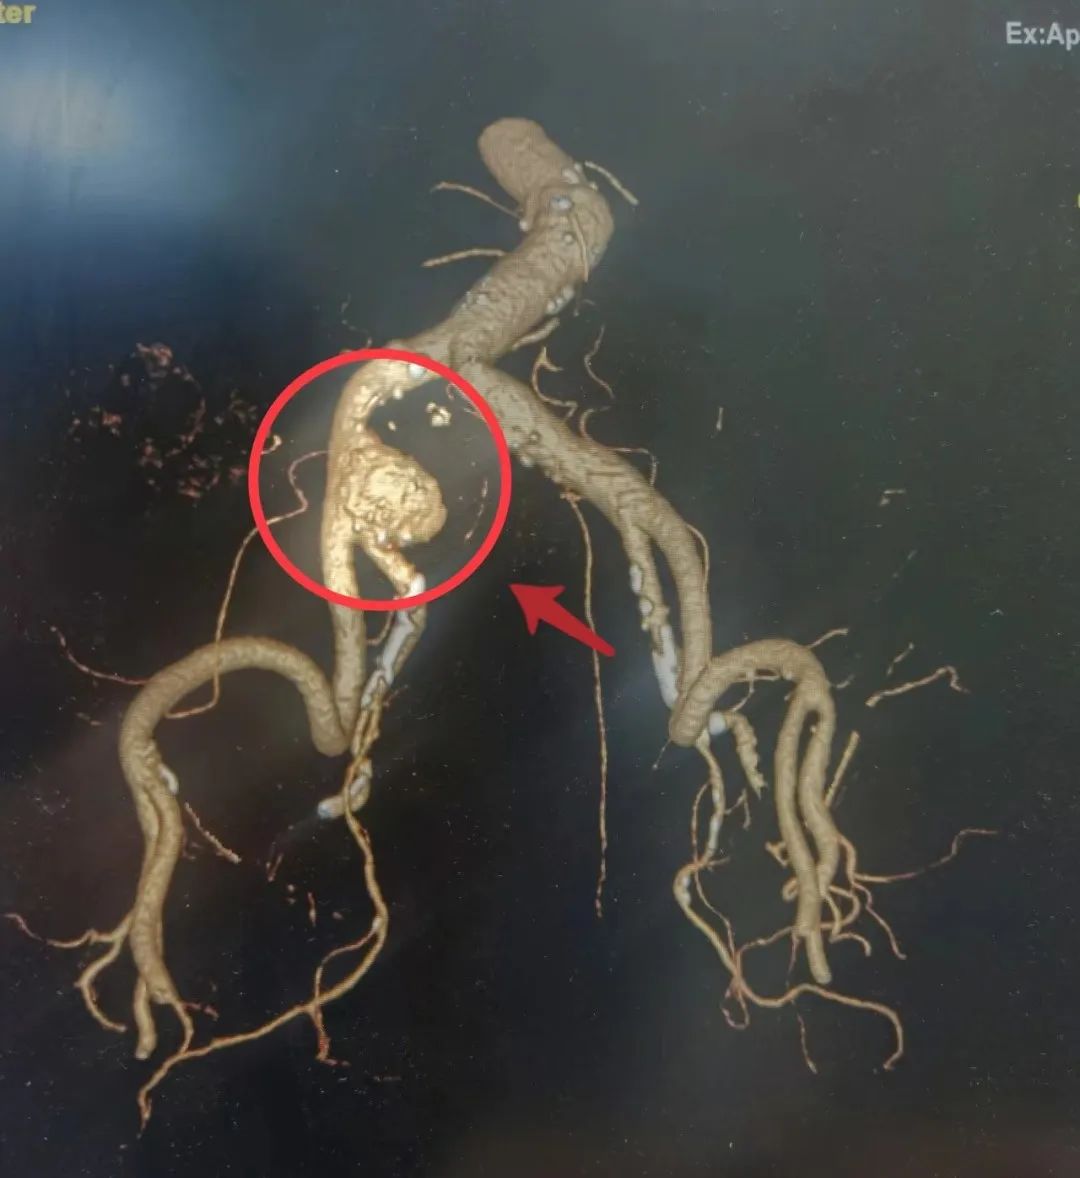

因阵发性腹痛2月余,家住谢家集区的陈奶奶(化名)在家人的陪伴下就诊广济医院,CT腹部平扫,发现“右侧髂总动脉瘤,局部夹层可能”。完善CTA检查,明确患者动脉瘤位置、直径,见:右侧髂总动脉局部增宽,并可见囊袋影向外突出,瘤颈宽约24mm,瘤体高约25mm。

▲术中图